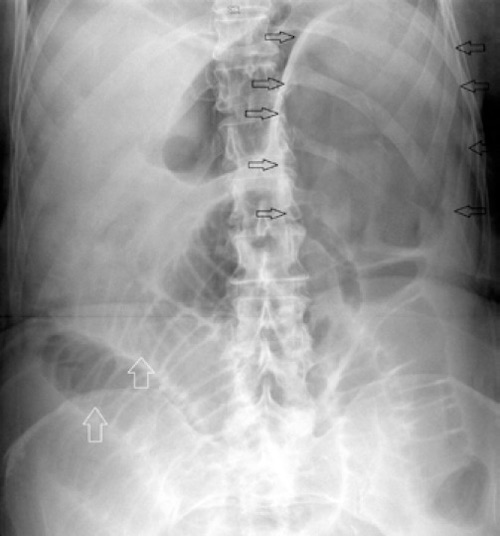

- Abdominal Plain Film Can Be Diagnostic But is Neither Sensitive nor Specific

- Classic “Coffee-Bean Sign” (Dilated Loop of Colon with Apex in the Left Upper Quadrant) is Rarely Seen

- Suggestive Plain Film Findings Should Be Further Evaluated by CT

- James B, Kelly B. The abdominal radiograph. Ulster Med J. 2013 Sep;82(3):179-87. (License: CC BY-NC-SA-4.0)